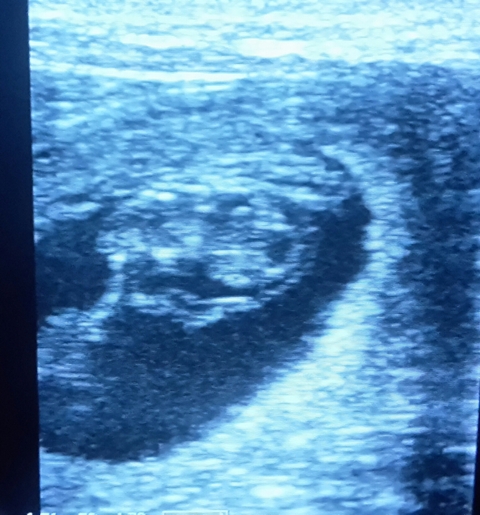

Wir kommen mit super Nachrichten vom Ultraschall, Velly ist schwanger.

Juchu, wir bekommen Baby´s und freuen uns riesig.

So sieht ein Winzling 4 Wochen nach dem decken aus.